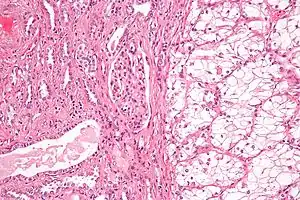

| Micrograph of the most common type of renal cell carcinoma (clear cell)—on right of the image; non-tumour kidney is on the left of the image. Nephrectomy specimen. H&E stain | |